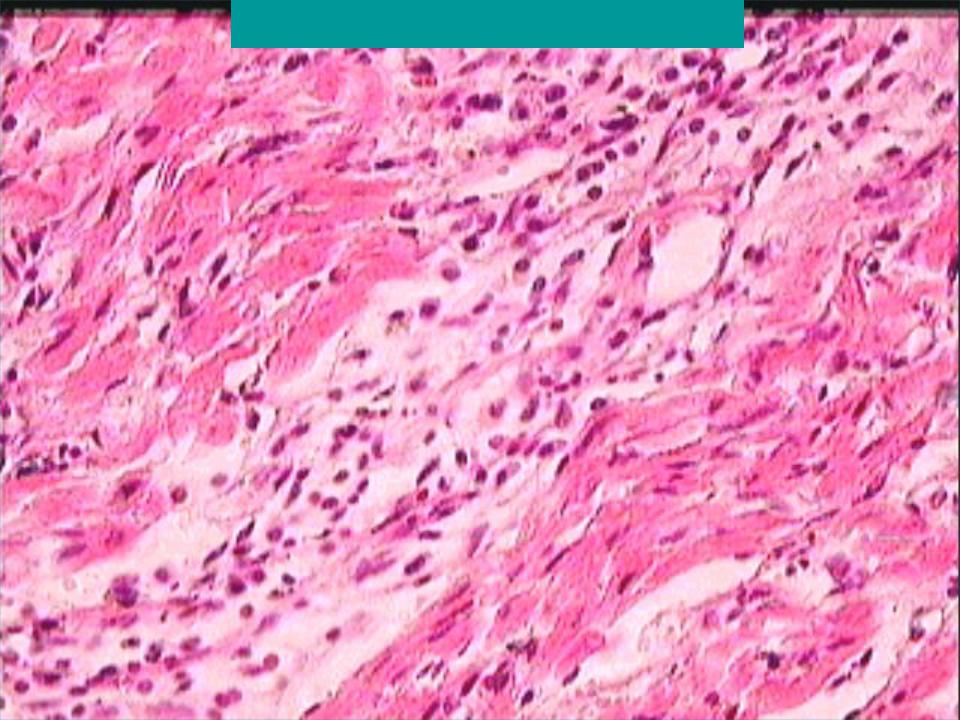

Межуточный миокардит: гистологические исследования

Раздел: Идеи и советы